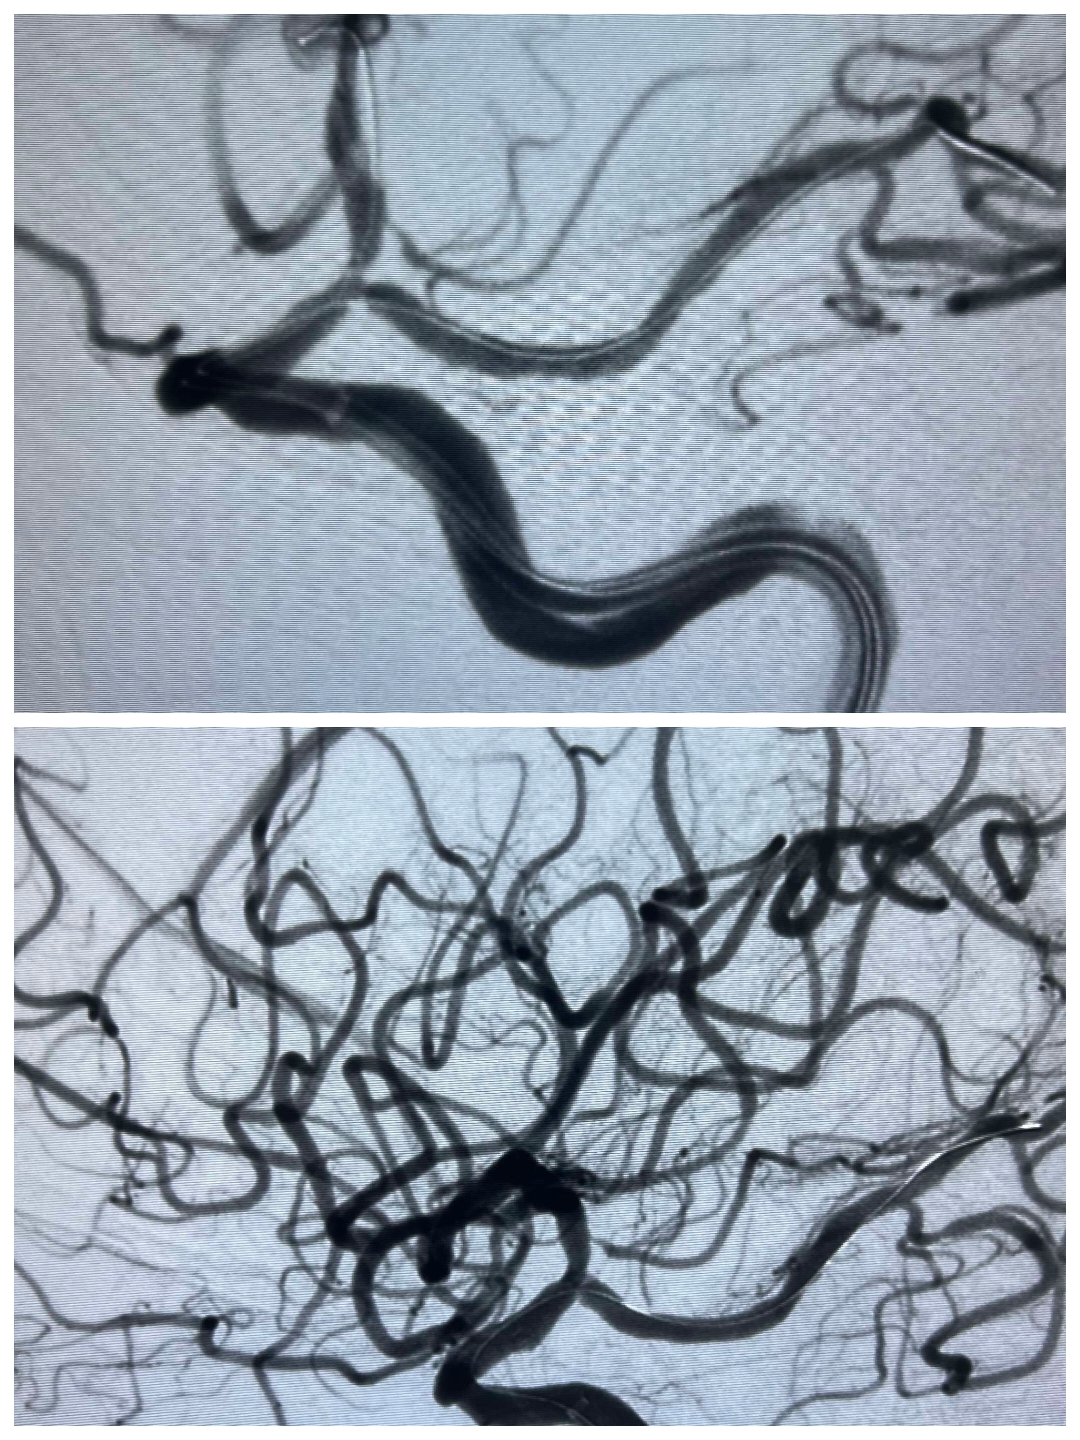

刘某,女性,69岁,因“视物模糊伴头晕不适一个月”入院。

MRI提示左枕叶脑梗塞,粗看MRA还可以,左侧血管较右侧血管稍稀疏纤细一点。

进一步DSA检查提示左侧颈内动脉末端狭窄~果然比MRA精准

予以双导丝双球囊扩张,稀疏的颅内血管终于开枝散叶。术后患者症状改善,治疗效果非常满意。